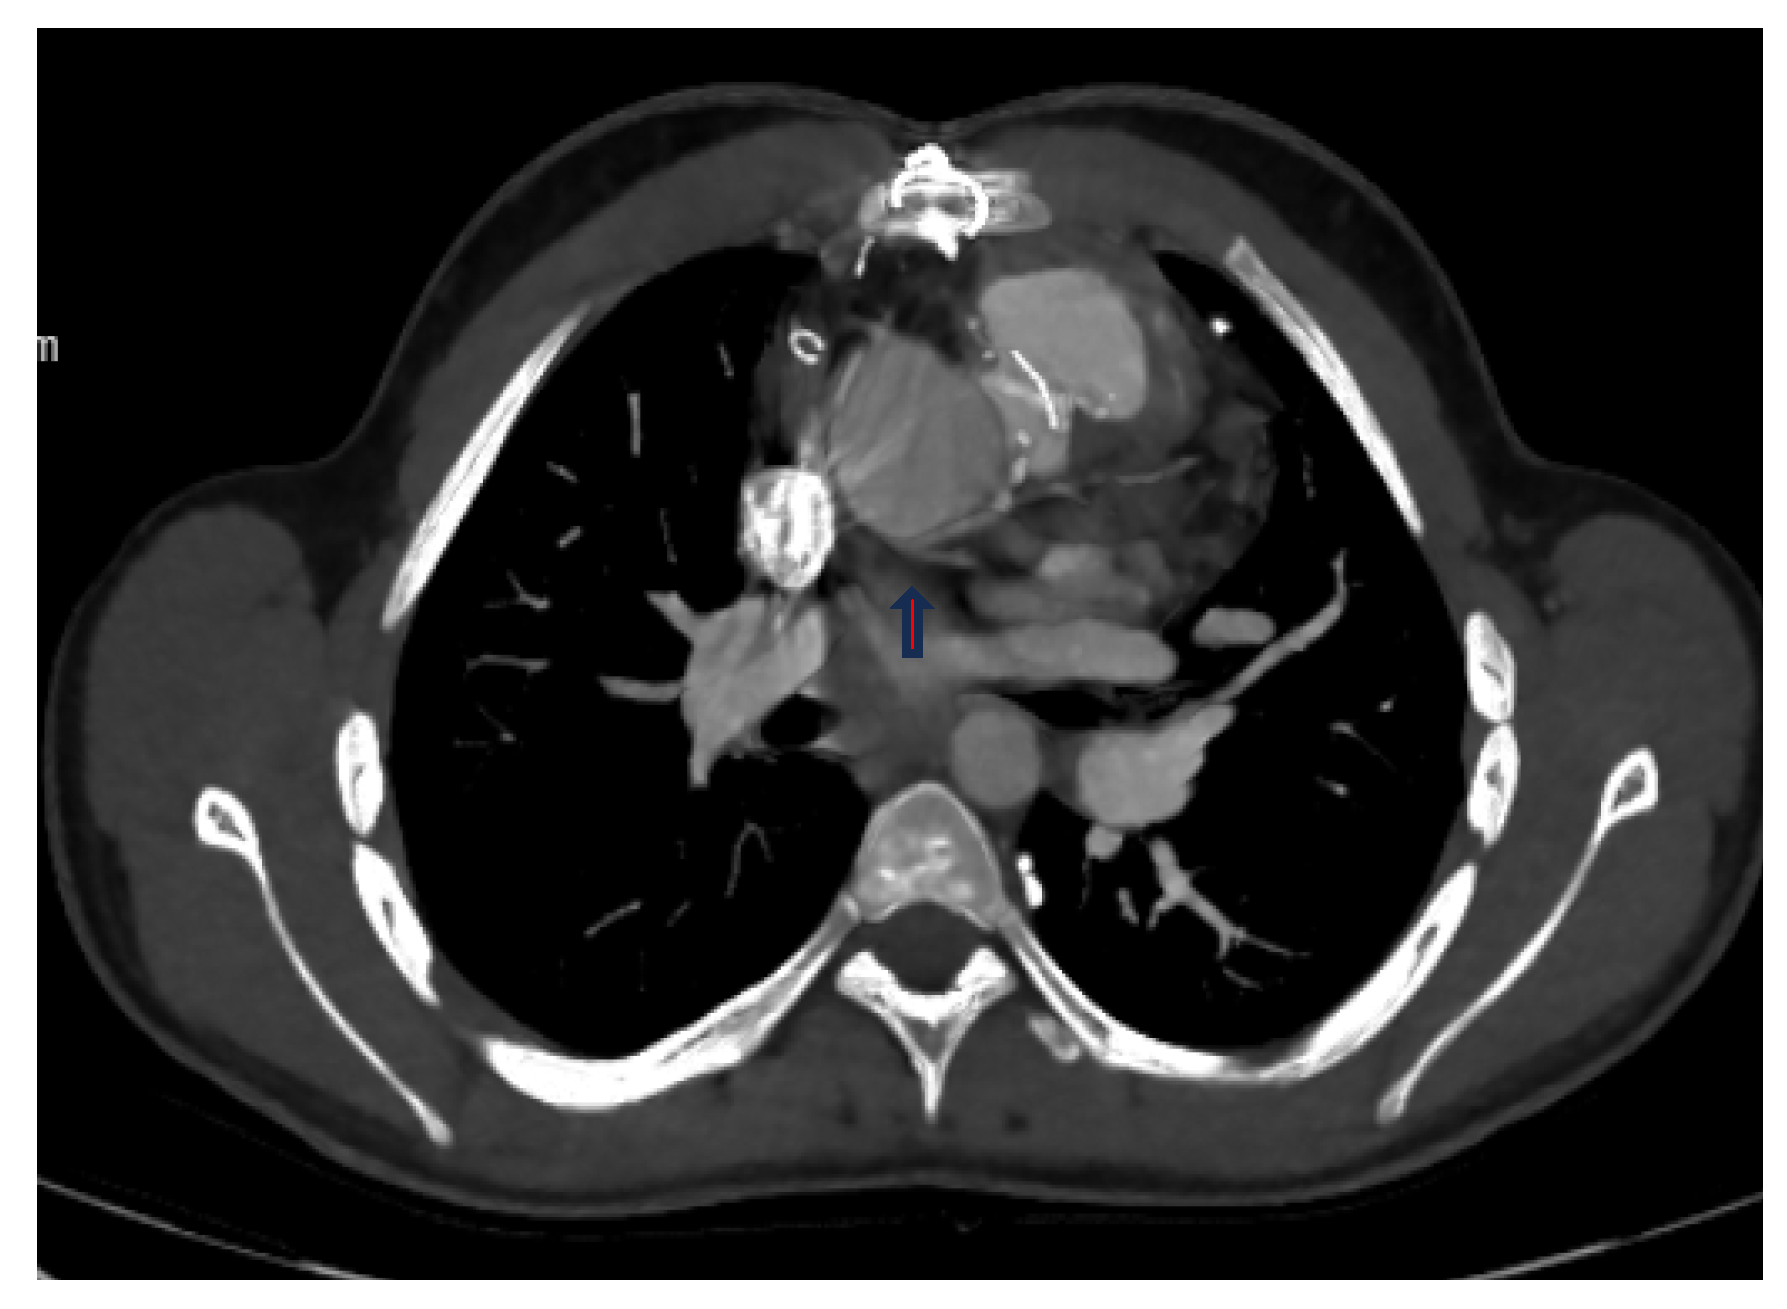

| Operated TGA (arterial switch) | Cx separated from the right coronary artery |

| Operated TGA (Rastelli) | Left coronary artery with interarterial course separated from the right coronary sinus |

| Single ventricle morphology (Fontan) | Cx leaving the right coronary sinus |

| Operated aortic stenosis, pulmonary stenosis (ROSS) | Left coronary artery leaving the right coronary sinus |